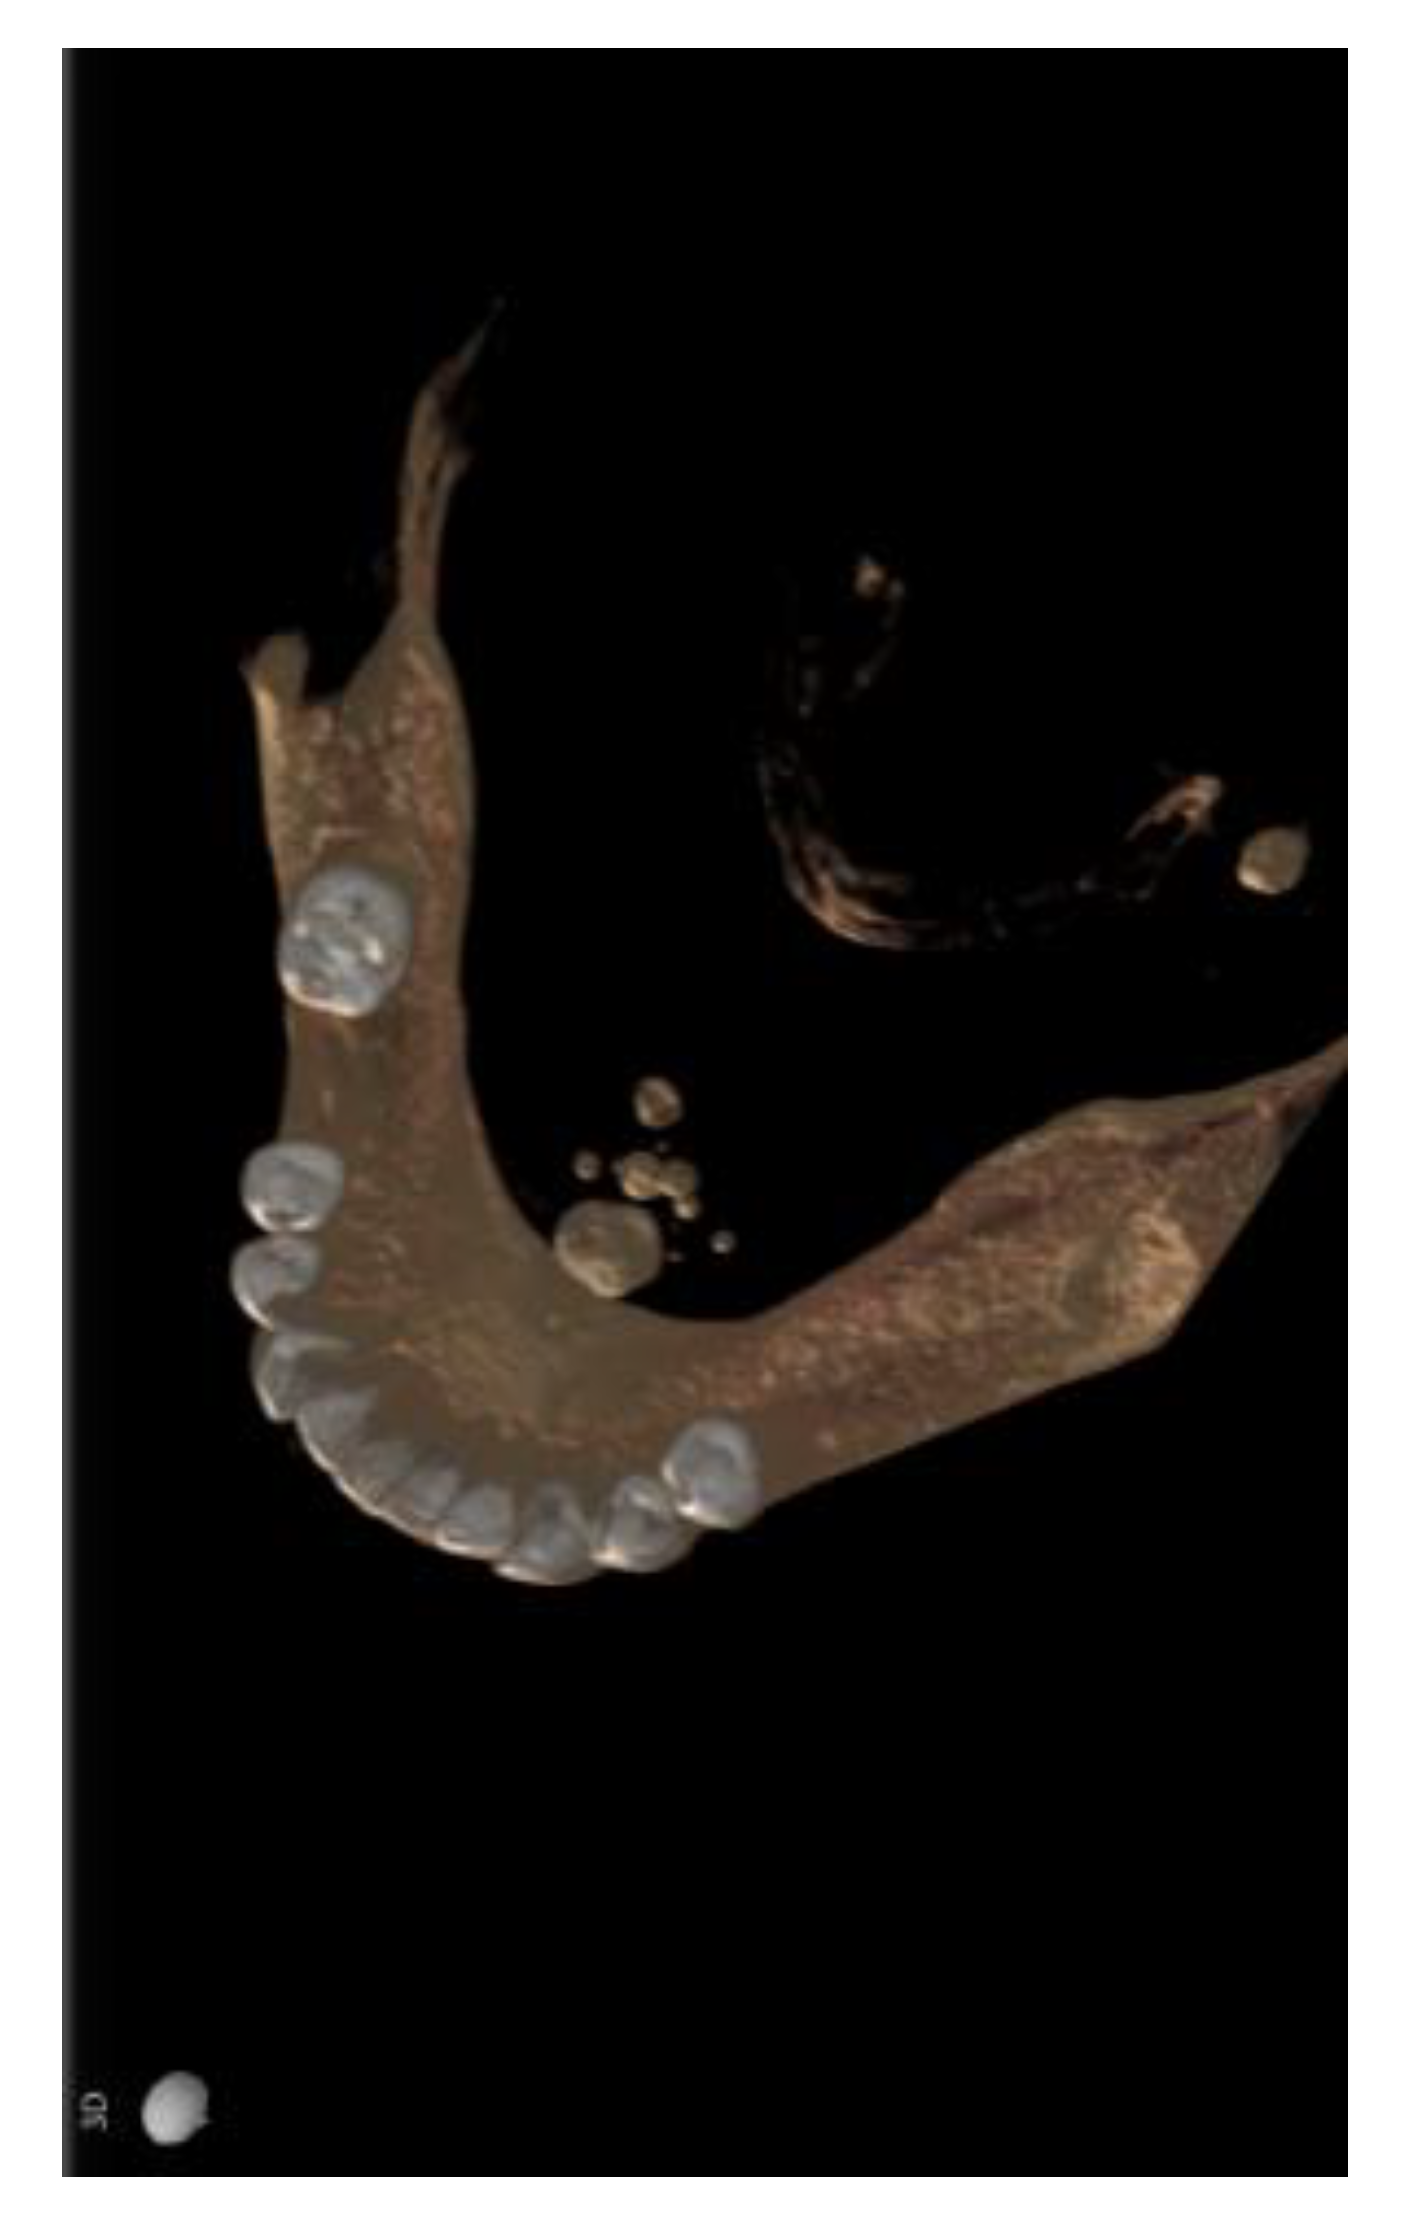

2. Case Presentation